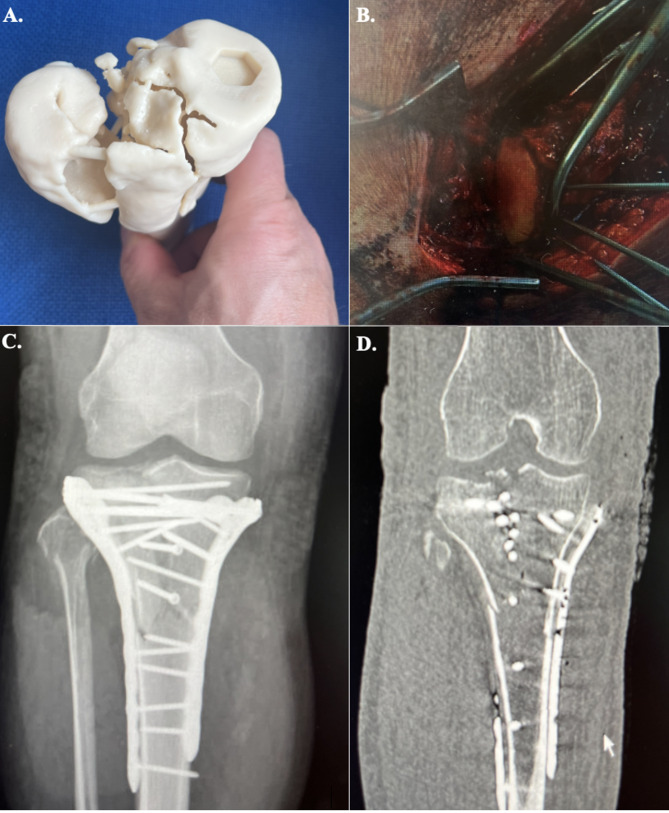

Main body: FEA involves several steps, including geometry representation, segmentation, 3D rendering, meshing, material property assignment, defining boundary conditions, and specifying contact conditions. The process utilizes patient-specific volumetric data-computed tomography (CT) scan, for example-and aims for a balance between computational efficiency and accuracy. FEA provides valuable outcome measures such as stress distribution, strain quantification, fracture gap motion, failure prediction, and implant stability. These measures aid in evaluating fracture fixation techniques, implant design, and the impact of different fixation strategies. FEA has found applications in femur and proximal humerus fracture fixation, distal femur fracture planning, tibial plateau fractures, and post-traumatic osteoarthritis. It plays a pivotal role in predicting fracture risk, assessing construct stability, and informing surgical decision-making. Additionally, FEA facilitates the development of custom surgical planning and personalized implants. To enhance accuracy, FEA is combined with cadaveric biomechanical analysis, providing a reference-standard representation of in vivo kinematics. Future research should focus on refining FEA models through increased validation using cadaveric models and clinical data.